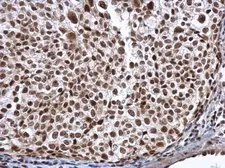

Images